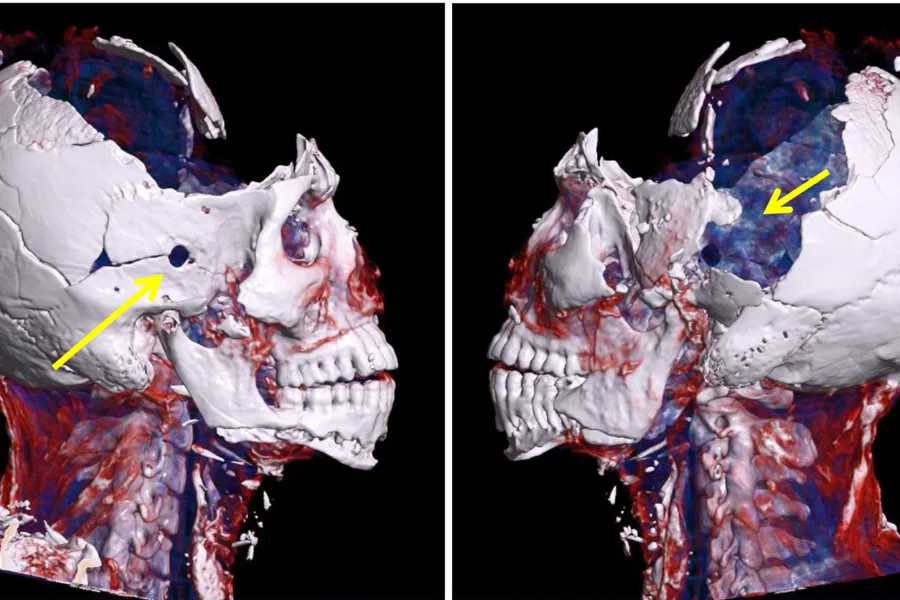

Fig 1. 3D CT-bilde av avdød funnet etter brann. Piler viser til innskuddsåpning i høyre tinning og utskuddsåpning i venstre tinning, begge deler usynlig forkullet hud.

Uten radiologiske undersøkelser hadde vi rettsmedisinere ofte stått på bar bakke. CT og MR gjør det lettere å påvise fremmedlegemer som prosjektiler eller hagl og viser brudd og luftansamlinger som vi kunne oversett dersom vi gjorde obduksjon alene.

Vi bruker 3D-rekonstruksjoner av CT-bilder aktivt. De er nyttige til bruk i rettssaker når en sak skal legges fram for folk uten medisinsk utdannelse. For aktørene og tilhørerne i retten kan for eksempel en 3D-modell av en hodeskalle med et prosjektil fra et skytevåpen være «renere», etterlate mindre voldsomme inntrykk og være lettere å forstå enn bilder av en dissekert hodeskalle og radiologiske snittbilder.